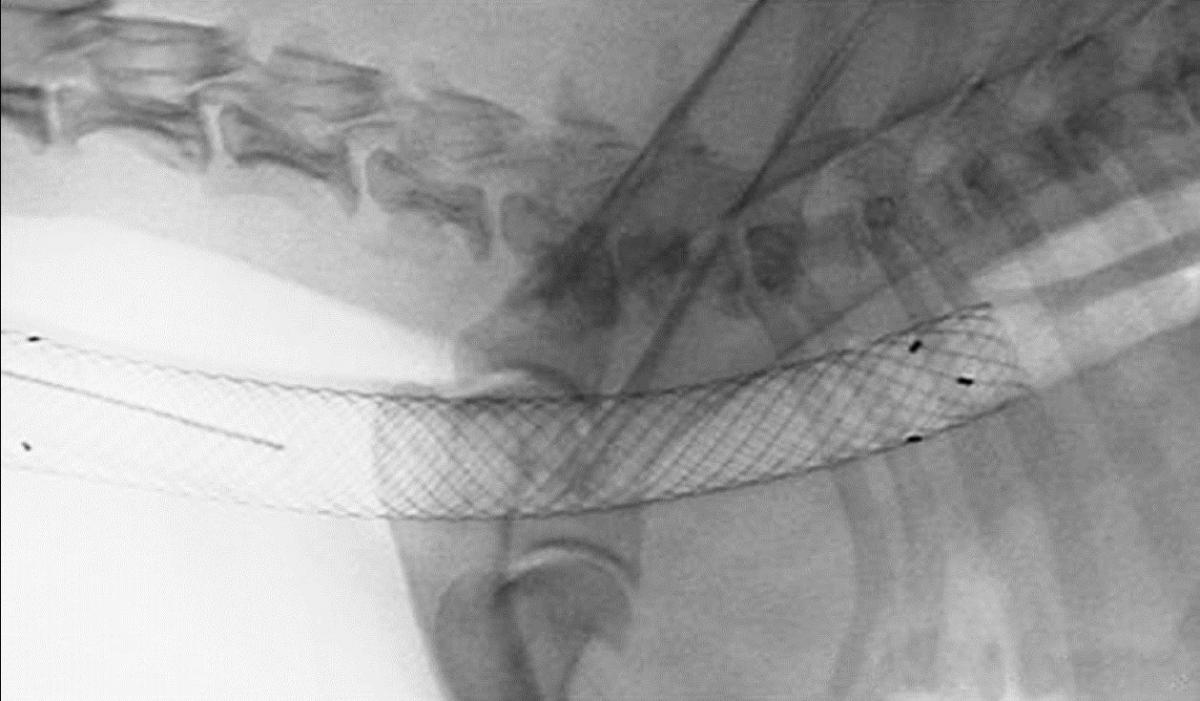

Bei der unblutigen, intraluminalen (innerhalb der Luftröhre) Technik wird das Stützgerüst direkt in das innere der Luftröhre eingebracht. Es handelt sich um ein Metallgeflecht aus einer Speziallegierung, das die Luftröhre von innen aufdehnt (Abb 1.). Das Metallgeflecht, der so genannte Stent wird in Narkose und unter Durchleuchtung im zusammengefalteten Zustand in die Luftröhre eingebracht. Wenn der Stent an die richtige Position vorgeschoben wurde wird dieser geöffnet und das Geflecht kleidet die innere Oberfläche der Luftröhre aus.

Diese Methode eignet sich besonders für im Brustkorb (intrathorakal) gelegene Trachealkollapse. Bei einem Kollaps der gesamten Trachea (Hals und Brustkorb) kommt ebenfalls diese Methode zum Einsatz.

Der Stent, also das Stützgerüst das in die Luftröhre eingebracht wird muss größenmäßig exakt auf den Patienten abgestimmt werden. Es ist daher in der Regel notwendig im Vorfeld der eigentlichen Stent Platzierung eine genaue Messung der Luftröhre in Narkose vorzunehmen.